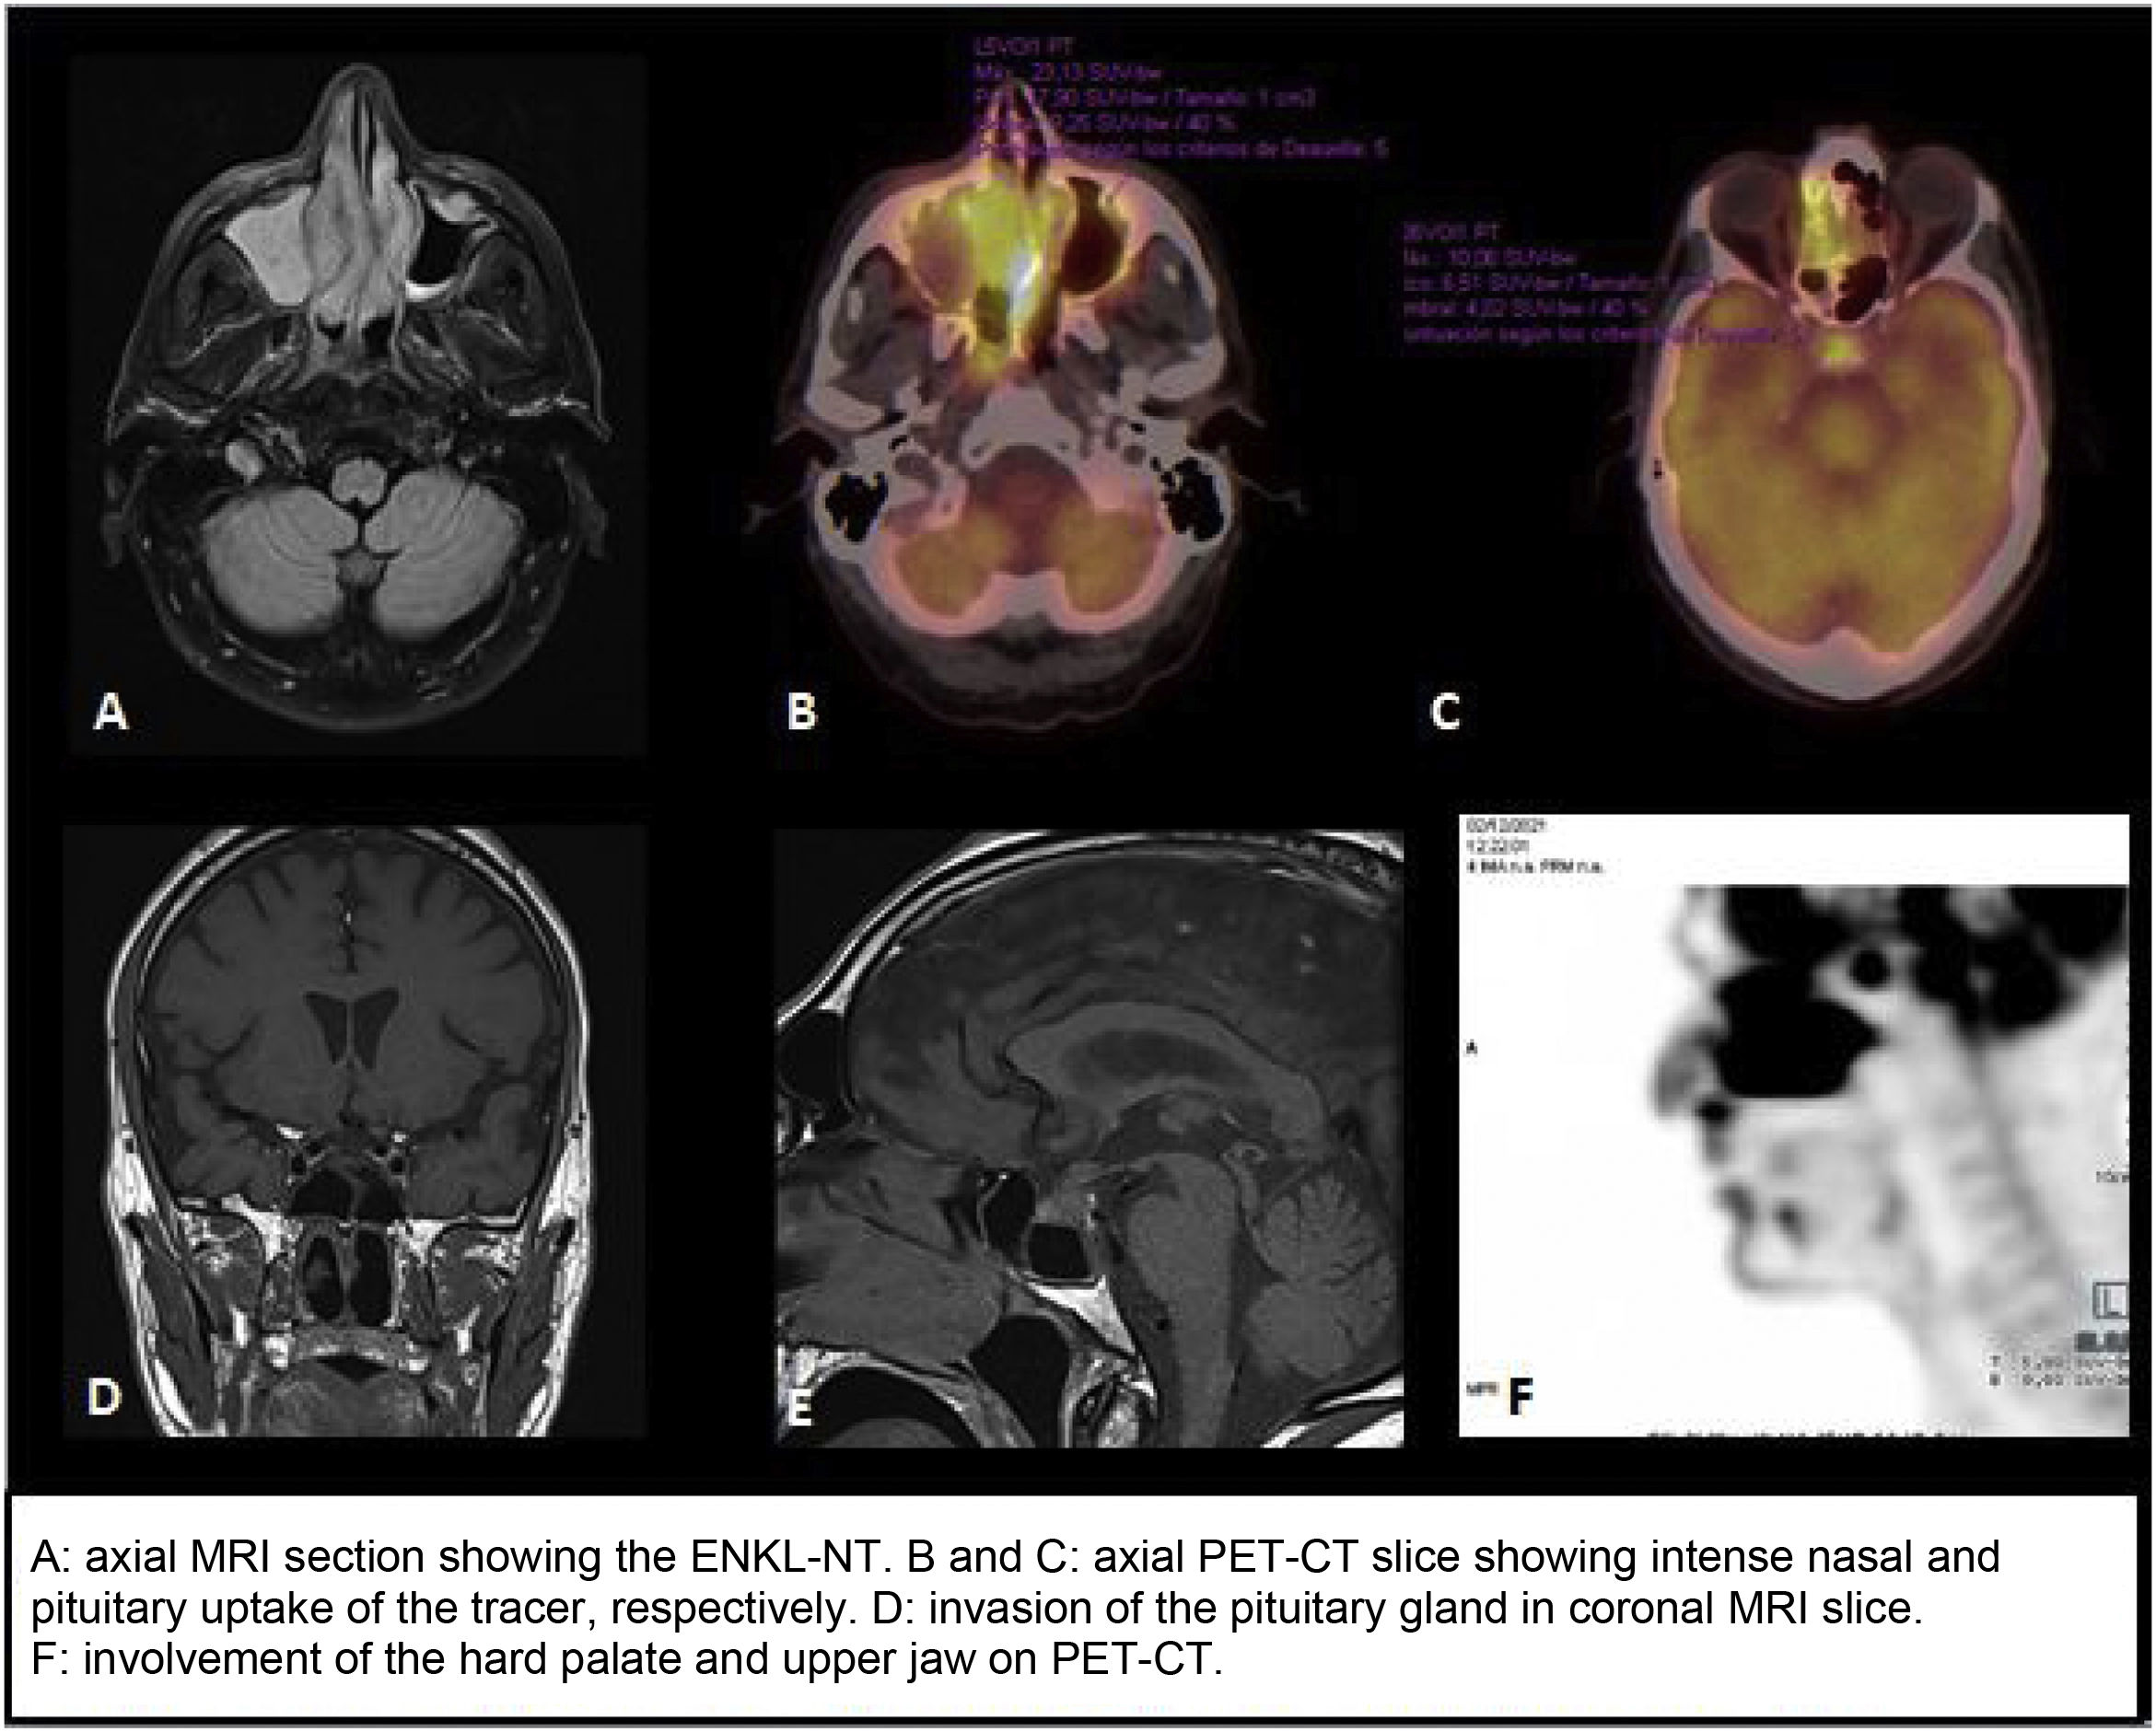

PET/CT scan with 18-fluorodeoxyglucose (FDG) showed marked metabolic activity, both nodal and extranodal, with intense pituitary uptake suggestive of tumour invasion (SUVmax 10.1) (Fig. 1), as well as a large sinonasal hypermetabolic mass and intense activity in the left L3, bilateral L5 and right S1 nerve roots (SUVmax 3.1), consistent with the patient’s symptoms of low-back pain. These results, in conjunction with those of the skin biopsy and LP, confirmed the diagnosis of stage IV ENKL-NT with skin and central nervous system involvement.